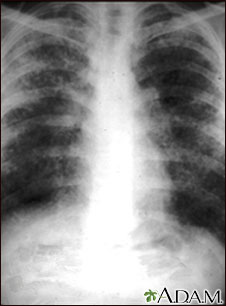

Different imaging tests may help diagnose sarcoidosis:

- Chest x-ray to see if the lungs are involved or lymph nodes are enlarged